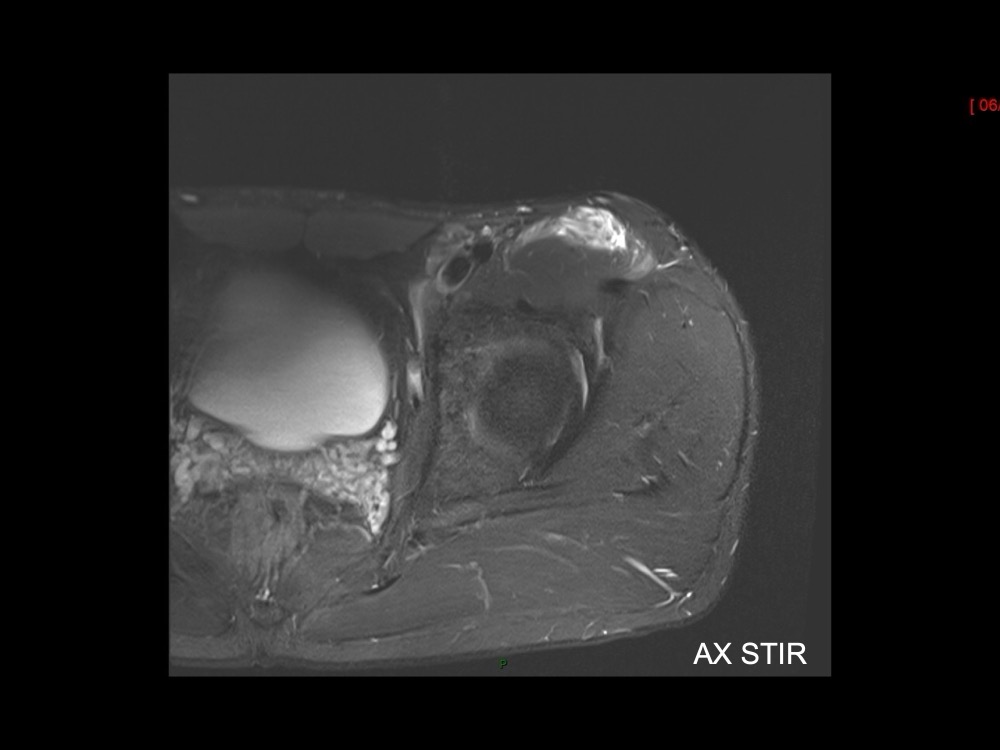

Moalla / Mihoubi-Bouvier / Drapé 18/05/2022